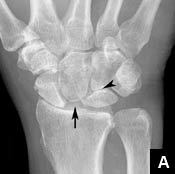

Stages of SLAC wrist

These begin at the radial aspect of the radioscaphoid joint (due to its major function in wrist loading), then the remainder of the radioscaphoid joint, and ultimately the capitolunate joint.